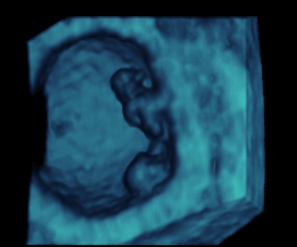

Ecografía 4D de un embrión de 8 milímetros de longitud